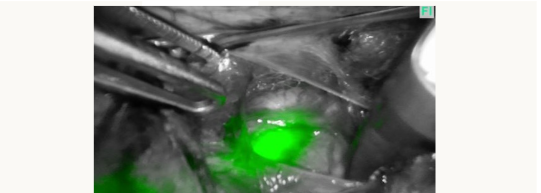

Figure 2A

Figure 2B

Helping to see the ureter more laterally in the pelvic sidewall can allow safe occlusion of the uterine artery at its source (figures 2A and 2B above) which can be helpful during myomectomies or more complex hysterectomies.

While the ICG dye does gradually pass into the bladder, it stays visible in the ureters for 4 - 5 hours as it seems to stain the urothelium (figure 3 above). We have found that no further intraoperative injections are necessary.